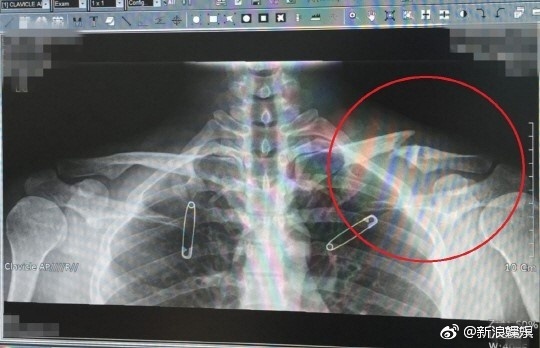

Ngoài chấn thương vai và khối u xương, cũng có thông tin Yoo Ah In bị gãy xương đòn bên trái từ hồi năm ngoái. Sở dĩ chấn thương xương đòn của anh ta không được công bố sáng tỏ là bởi Yoo Ah In đã dùng thuốc giảm đau và tham gia vào một sự kiện thuộc liên hoan phim ngay sau một ngày xảy ra tai nạn.